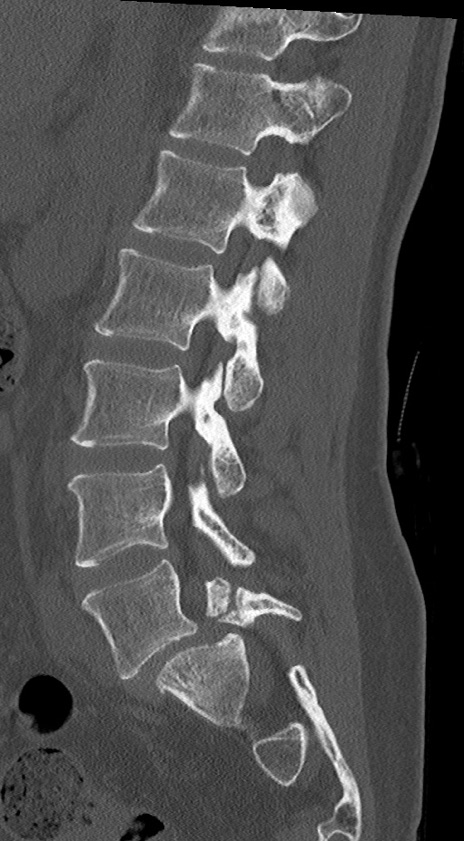

【整形】TIPS症例4 腰椎CT(矢状断像)

腰椎CT

冠状断像